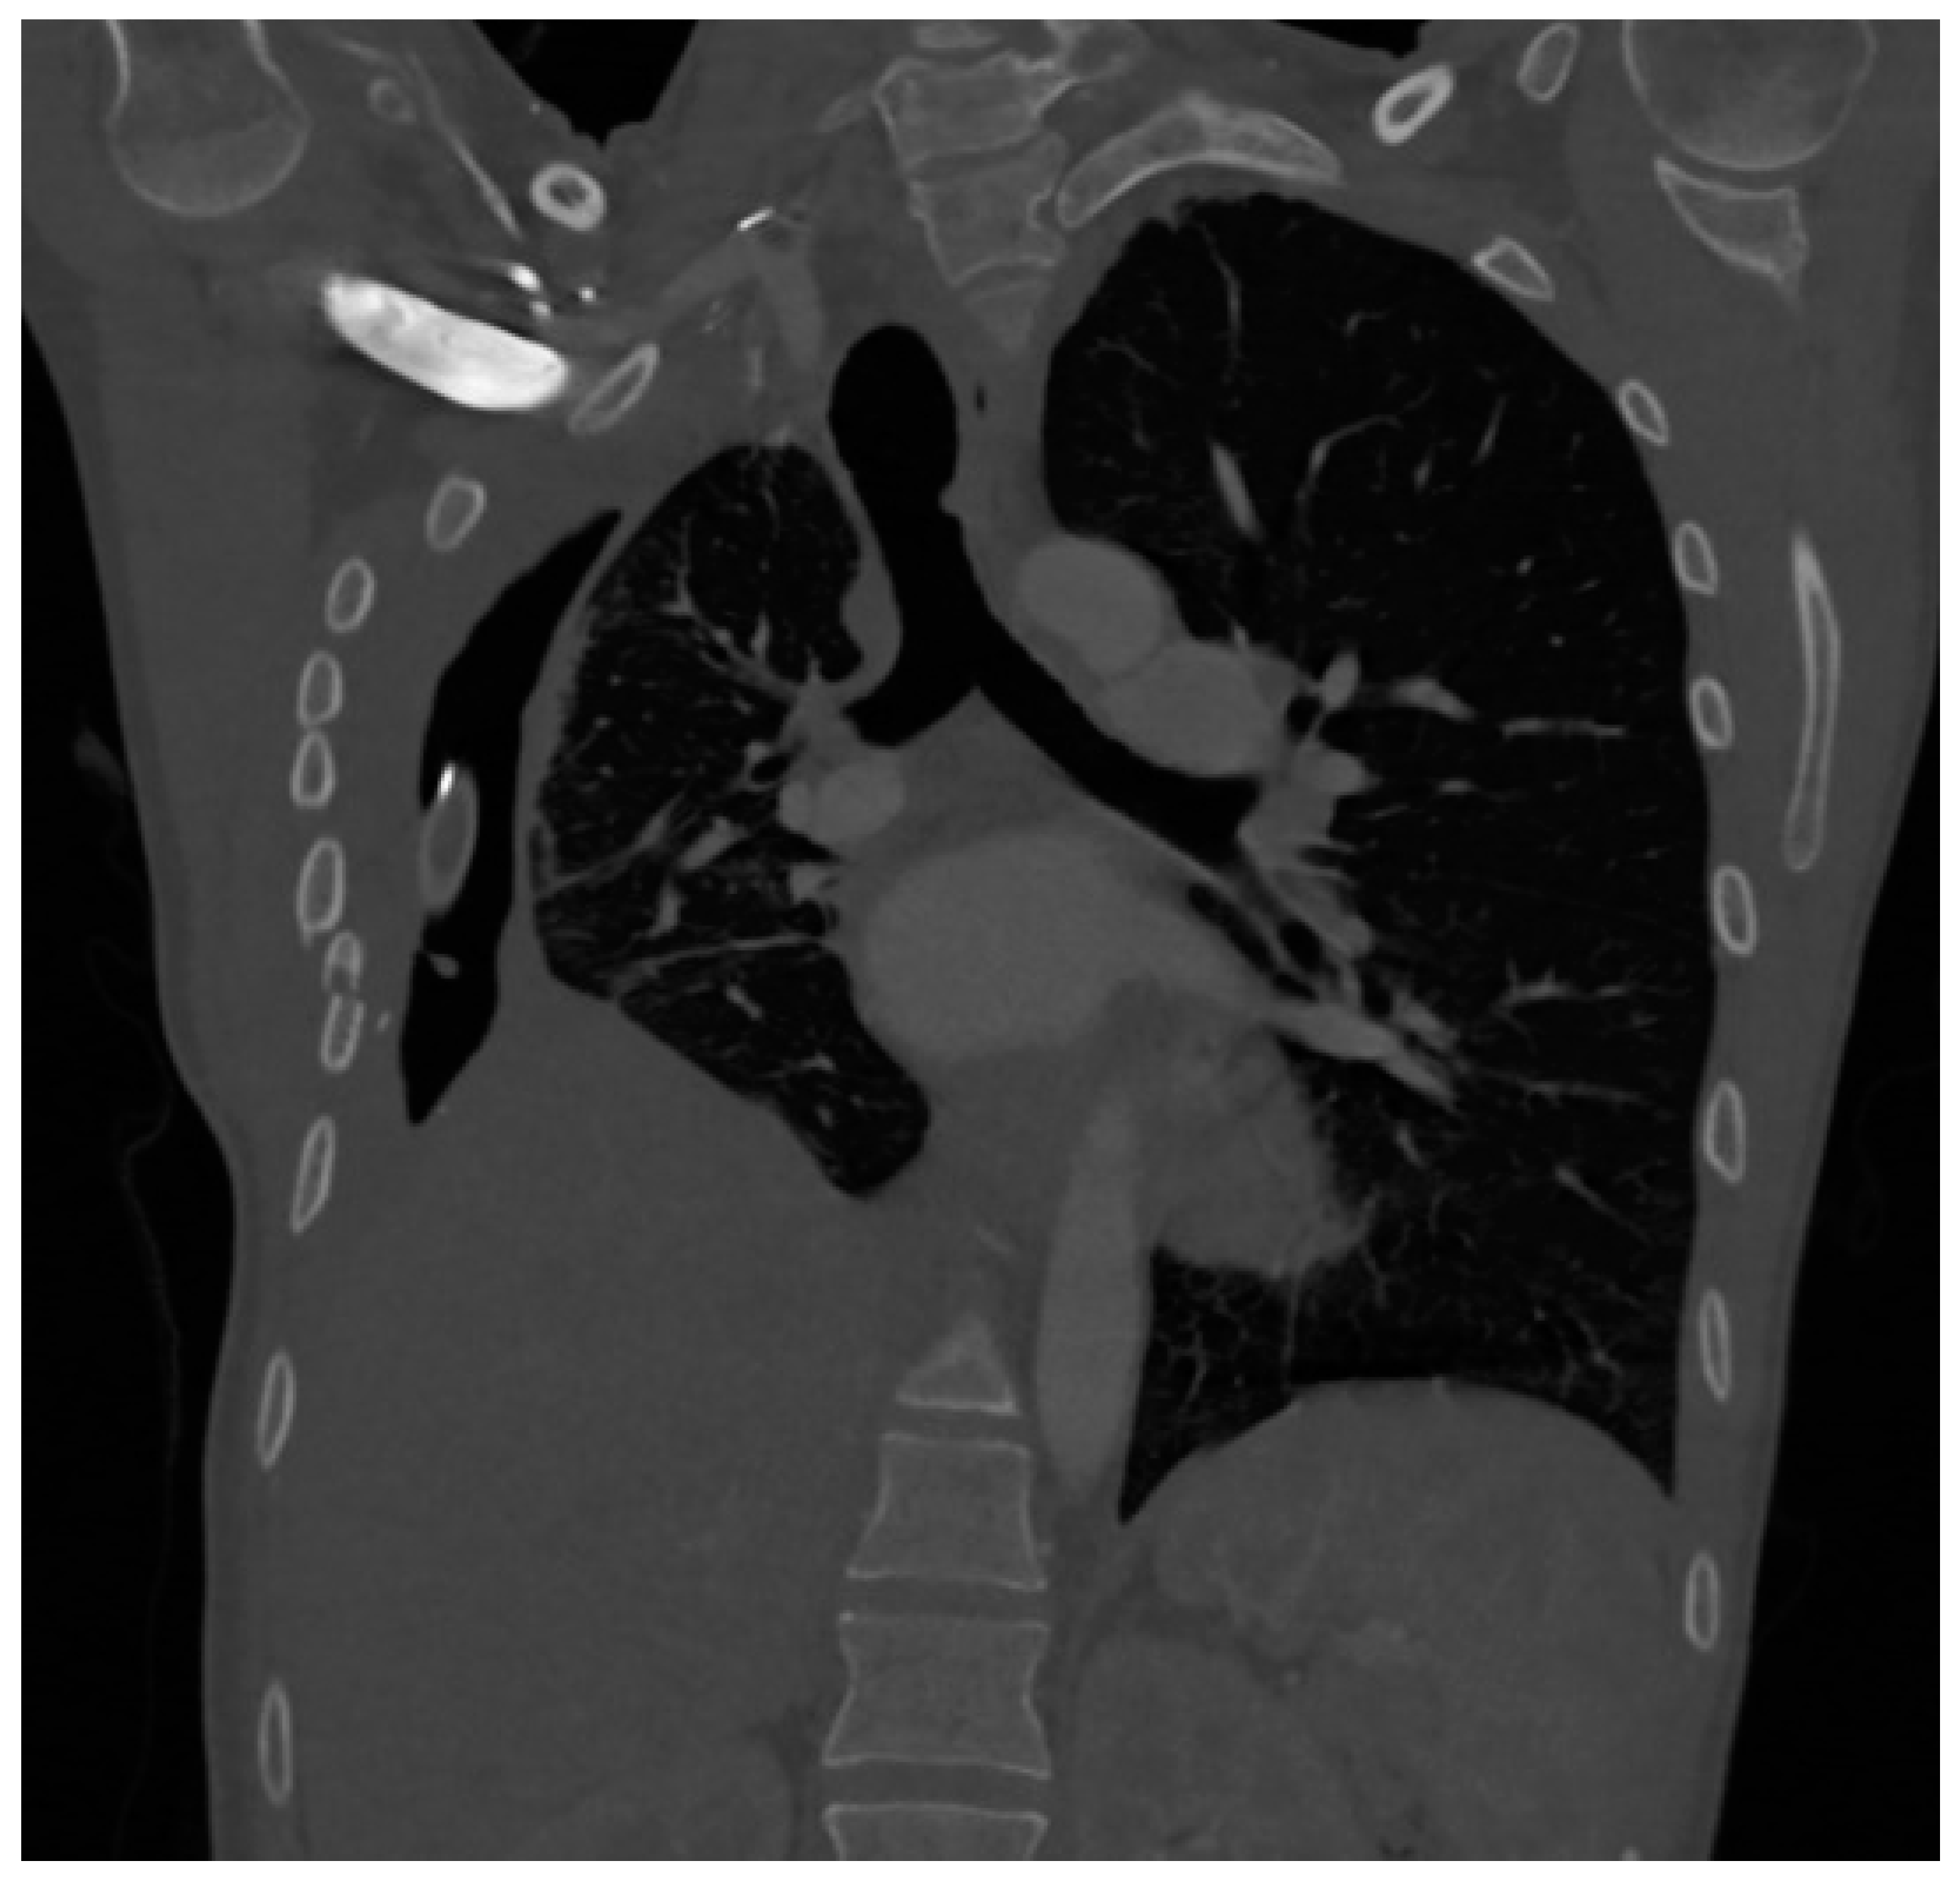

The patient was then transferred to the ICU in our facility. Cultures obtained from her nasal swab as well as her anal swab were positive for Klebsiella pneumoniae. The remaining microbiological findings as well as her antibiotic therapy are presented in Table 1. She had also been surgically evaluated and underwent evacuation of empyema, decortication of the right lung, and finally lower right lobectomy, on the 16th day of hospitalization. She was transferred back to the ICU with drainage of the right pleural cavity. A CT scan image is presented in Figure 4.

Figure 4. CT scan of the patient 2 at admission to the ICU.